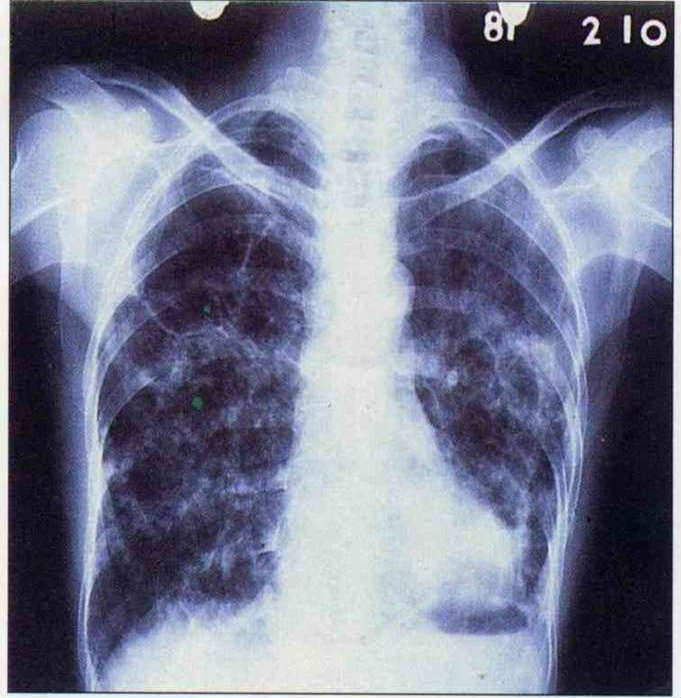

也有人直覺地把日益嚴重的空氣汙染、廢氣瀰漫,聯想為結核病死灰復燃的禍首。醫師多認為此說無關,因為肺結核係結核菌經由飛沫傳染,「吸進過多汽車廢氣或化學汙染,X光片上的黑點恐怕就是癌症了!」林道平表示。